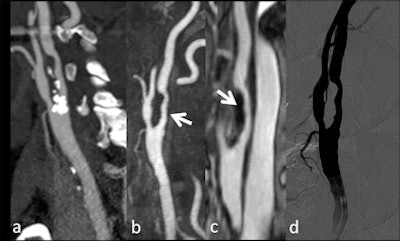

| Patient with dissection of brachiocephalic arterial trunk and right common carotid artery. A, B: Time-resolved sequences allow the visualization of an asymmetric transit time of the contrast agent, showing delayed opacification of right common and internal carotid artery compared to the normal left vessels. (Provided by Prof. Carlo Catalano and Dr. Beatrice Cavallo Marincola) |